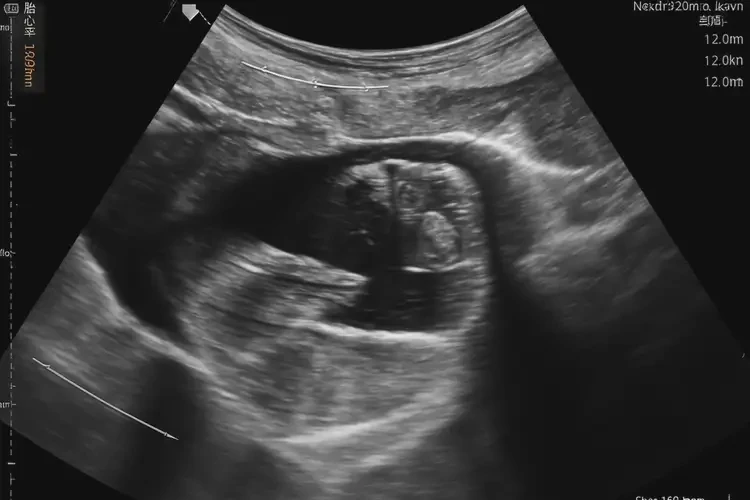

孕18周3天胎心率160多還能保住嗎(圖1)

孕18周3天胎心率160多還能保住嗎(圖2)

孕18周3天胎心率160多還能保住嗎(圖3)

孕18周3天胎心率160多還能保住嗎(圖4)